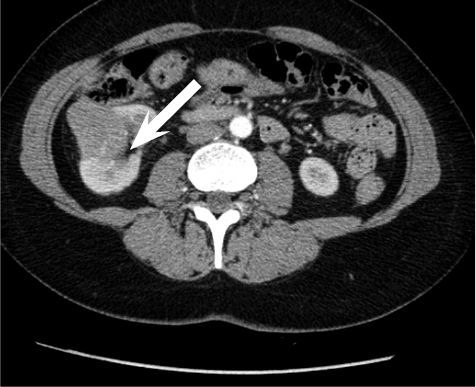

A 52 year old woman arrived at a hospital for a routine health check-up. Abdominal ultrasound revealed a 4.5 cm diameter lesion in the right kidney. Patient was directed to perform a contrast-enhanced computed tomography (CT), which was performed to specify the nature of the formation. CT found 49 mm x 34 mm cyst in the middle-lower portion of right kidney with septum and contrast accumulation (Figure 1), it was classified as Bosniak III and partial nephrectomy was chosen as a main choice of treatment.

Figure 1. A contrast-enhanced Computed Tomography of abdomen was performed (a 49 mm x 34 mm cyst in the middle-lower portion of right kidney with septum and contrast accumulation was found (white arrow)